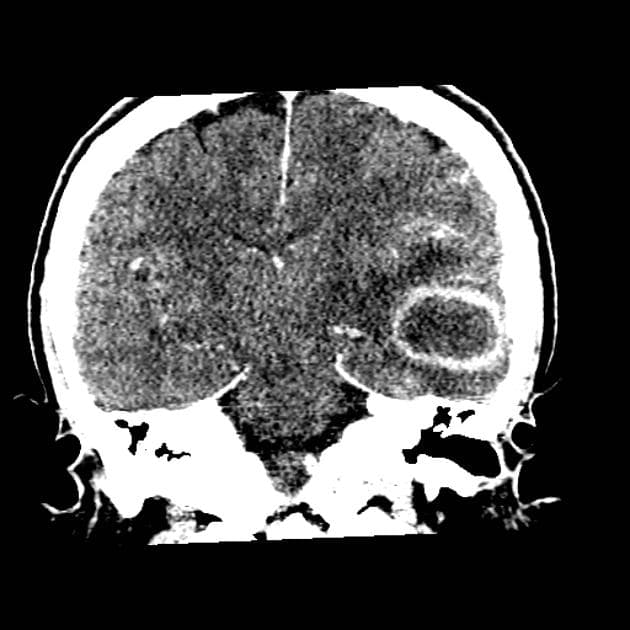

- Khối bắt thuốc dạng viền (ring-enhancing mass) ở thuỳ trán sau bên trái, kèm theo một lượng nhỏ phù vận mạch (vasogenic edema) xung quanh.

- Có một phần hạn chế khuếch tán (diffusion restriction) ở vùng ngoại vi, nhưng không có ở trung tâm.

Lesion "hoàn hảo" bắt thuốc dạng viền, nhưng không phải là áp xe não (do không có hạn chế khuếch tán ở trung tâm trên hình ảnh khuếch tán – DWI và lượng phù tương đối ít). MAGIC DR là từ viết tắt gợi nhớ hữu ích cho hình ảnh này.

- "Các khối u thứ phát bắt thuốc dạng viền có thể bắt chước áp xe não trên hình ảnh, nhưng hạn chế khuếch tán ở trung tâm gợi ý áp xe hơn là u thứ phát."

- "Lượng phù xung quanh tổn thương ít tương đối so với kích thước gợi ý u thứ phát hơn là u thần kinh đệm độ cao."